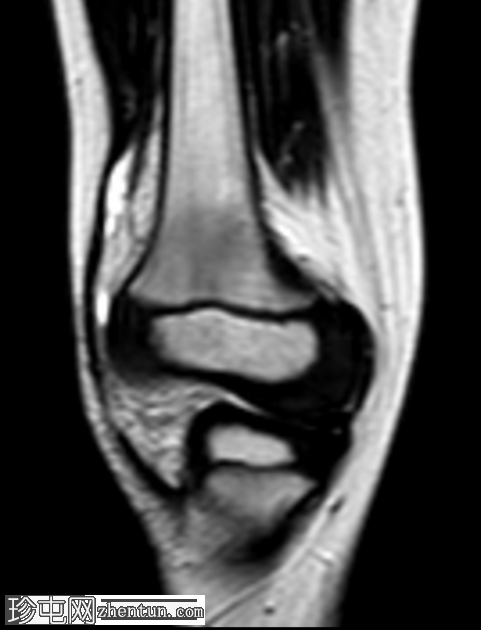

1.png

冠状位

STIR序列

右膝专用MRI显示股骨外侧髁后方髓内有一边界清晰的病灶,大小为1.6 x 0.9 cm,中心T1呈低信号,T2/STIR呈高信号,周围可见薄层T1高信号环(半影征)。

周围骨髓水肿广泛,在STIR序列上呈高信号,在T1加权像上呈低信号。